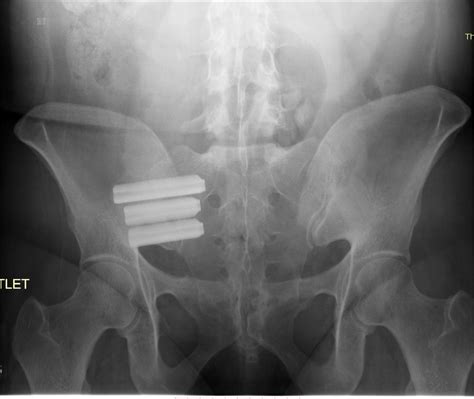

The most common and effective procedure for addressing SI joint pain is minimally invasive SI joint fusion. Unlike traditional open back surgeries that required large incisions and long hospital stays, modern Si Joint Surgery is performed using small incisions and specialized implants.

3. Implant Placement: Guided by fluoroscopy (real-time X-ray imaging), the surgeon places titanium implants across the SI joint to bridge it.

4. Fusion: These implants hold the joint in a fixed, stable position, allowing the body to naturally grow bone across the joint, permanently fusing it.